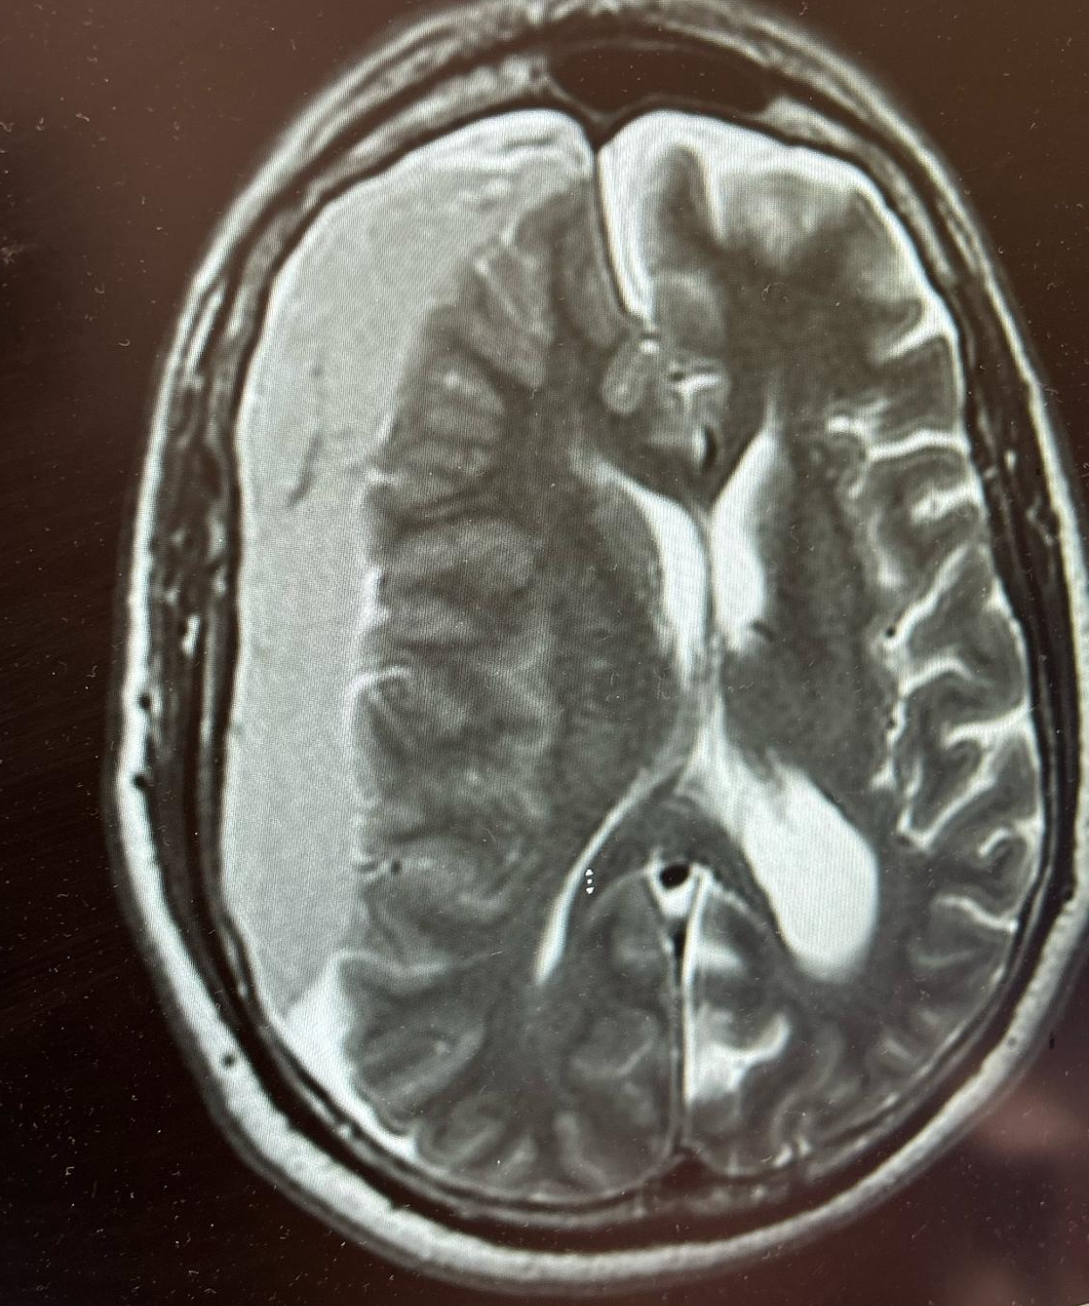

Strokes and Management

What I think you should known regarding the types of strokes and management

Strokes and how to manage them!